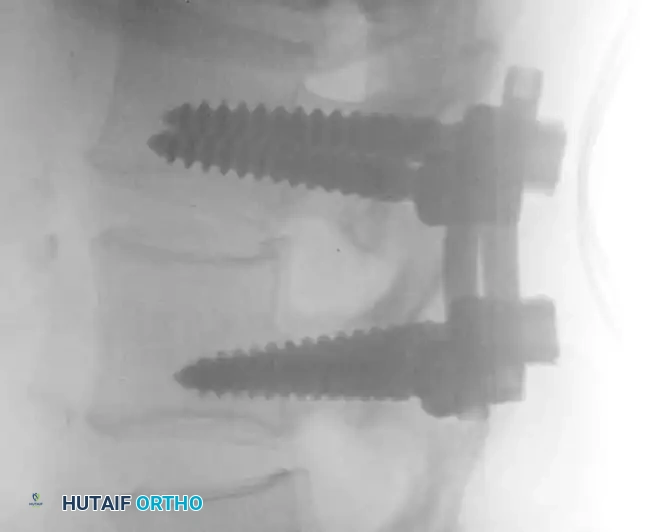

5. Pedicle Screw Instrumentation and Fluoroscopic Verification

• Pedicle screws are placed bilaterally into the cephalad and caudal vertebrae. The entry point is typically at the intersection of the pars interarticularis, the superior articular facet, and the transverse process.

• The pedicles are cannulated with a gearshift probe, palpated with a ball-tip feeler to ensure no cortical breaches, tapped, and the screws are inserted.

• Intraoperative fluoroscopy is absolutely critical during this phase to confirm trajectory and depth.

Image

Intraoperative AP fluoroscopy demonstrating the initial placement and medial trajectory of the pedicle screws within the vertebral bodies.

Lateral fluoroscopic view showing the depth of the pedicle screws. The screws should parallel the superior endplate and penetrate 50-80% into the vertebral body without breaching the anterior cortex.